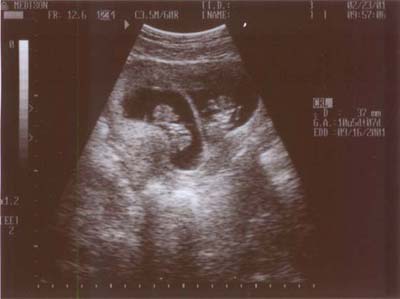

Sonogram on 23 FEB 2001 - Week 10

You should be able to make out the two amniotic sacs. Baby A is on the left.